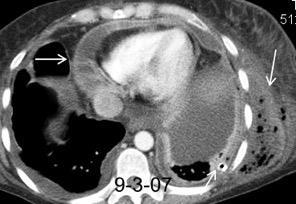

Masa axilar izquierda y derrame pleural derecho. Implantes pleurales, paraespinales . Ganglios en mamaria interna. Linfoma B difuso

Linfoma NH de cél. B. Invasión Transtorácica.

Afectación axilar